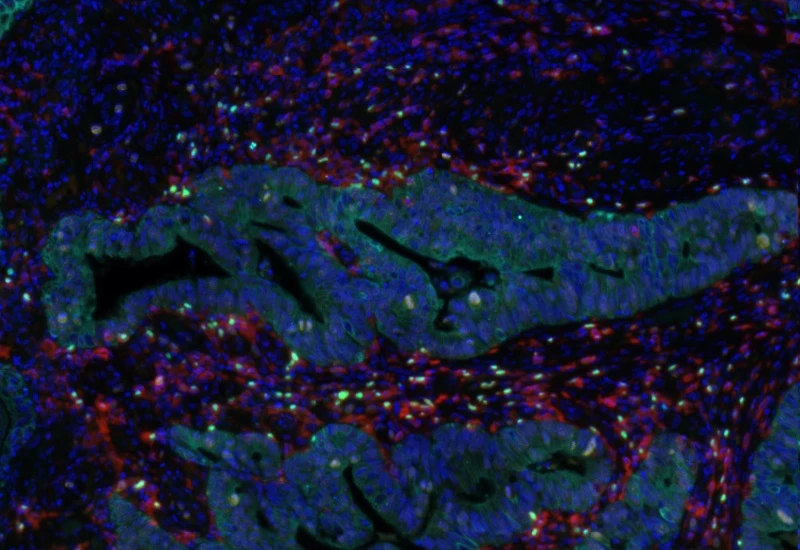

IF Immune status in situ

Characterize immune cell phenotypes relative to detected metastructures (e.g. tumors, glands), define distance ranges, measure cell-to-boundary distances inside/outside, and export up to 20 intensity, statistic, and morphometric parameters per cell compartment.

colon cancer, cytotoxic t cells, tumor microenvironment, PD1, CD8, spatial analysis, fluorescence

The IF Immune Status in Situ App provides phenotypic characterization of immune cells in reference to detected metastructures (e.g. tumors, glands) and measures the distance of detected cellular objects to the metastructure boundary (within and/or outside). Distance ranges can be defined. Each segmented cell compartment is measured for up to 20 intensity, statistic and morphometric parameters, as is the distance of each cell to the areas boundary.

Original image